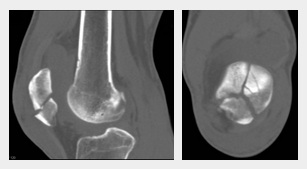

Gebrochene Kniescheibe, Röntgenfoto

Gebrochene Kniescheibe, Röntgenfoto [4]

Der Bruch einer Kniescheibe provoziert sofort Schmerzen, das Gehen ist beeinträchtigt oder gar nicht mehr möglich (48''). Äusserlich sieht man eine Schwellung, oft ist eine Hautschürfung vom Unfall vorhanden (1'0''). Dann kommt das Röntgenbild (1'8'') [web03].

Wenn das Röntgenbild nicht ausreicht bzw. der Bruch auf dem Röntgenbild nicht sichtbar ist, wird noch ein CT gemacht, selten noch ein MRT (1'22''). Dann sieht man die Details. Der Bruch der Kniescheibe kann sein

-- ein Teilabriss

-- ein Querbruch

-- ein Längsbruch (1'32'') [web03].

Ausserdem wird noch unterschieden, ob der Bruch "verschoben" oder "nicht verschoben" ist (1'36'') [web03].